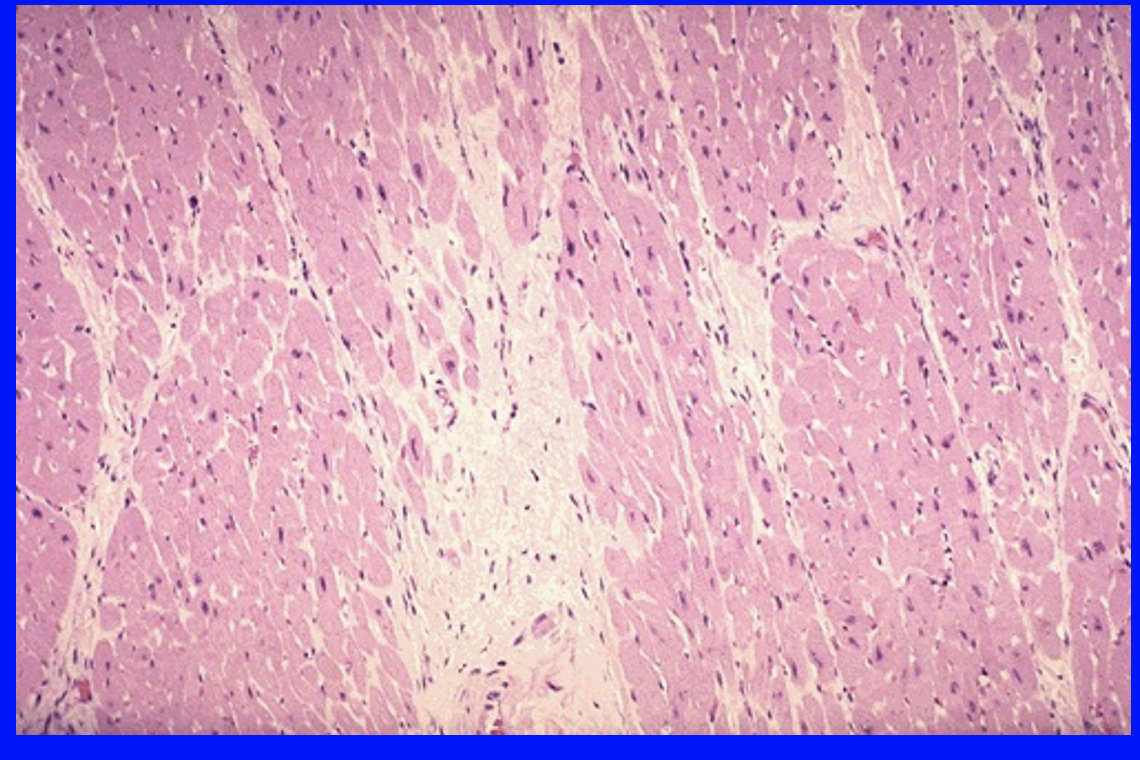

16

Q

What histological changes are seen 1-2 weeks post-MI?

A

granulation tissue, new blood vessels, myofibroblasts, collagen synthesis

17

What histological changes are seen >2 months after anMI?

strengthening, decellularising scar